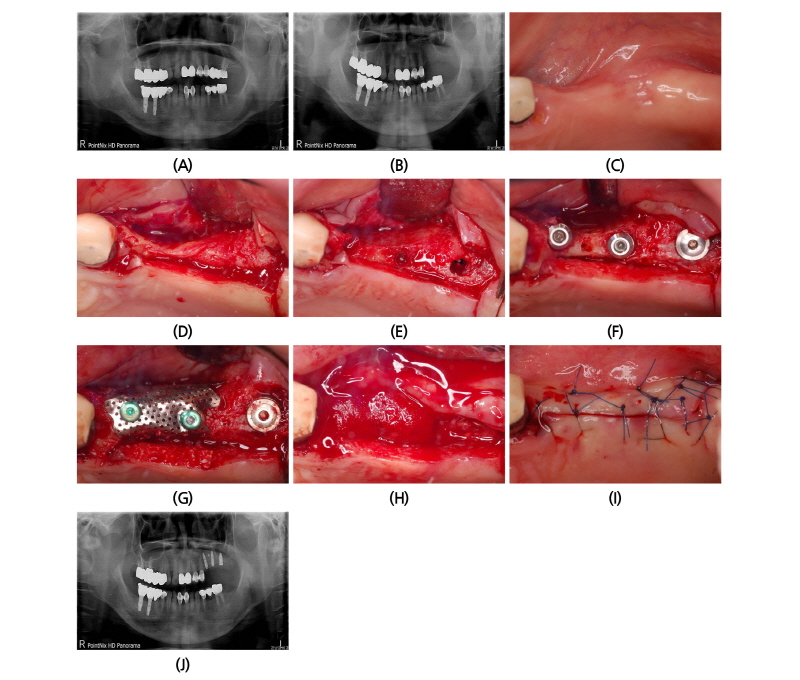

57세의 여성 환자가 상악 좌측부위 시린 증상을 주소로 내원 하였다. 파노라마 촬영과 구강 내 검진 결과 #26의 보철물 하방의 우식이 관찰 되었고 #22, 23-26의 브릿지를 제거한 결과 #26의 우식이 심하여 발치가 추천되었다(Fig. 5A).

발치 후 7주후 임플란트 식립을 위하여 환자가 재내원하였다. 재촬영한 파노라마 상에서 #26부위의 상악동의 함기화가 빠르게 진행되어 상악동 거상술과 골이식술이 필요하게 되었다. 예상과 달리 임플란트 식립을 위한 판막 형성 후 #24, 25 부위에 임플란트 식립이 불가능할 정도의 좁은 치조제가 관찰 되었으며 #26부위도 빠르게 치조제의 흡수가 관찰되었다(Fig. 5B-5D).

임플란트 식립을 위한 드릴링 전에 협설 측으로 어느 정도 치조제 폭을 만들기 위하여 수평적인 골삭제를 실시하였다(Fig. 5E). 그 후에 #24부위는 치조제 위축이 심하여 드릴링 시 협측으로 드릴이 빠져나오게 되는데, 이때 핸드피스를 잡은 손을 구개측으로 밀면서 드릴링과 식립을 하여 25 Ncm의 초기고정을 얻었다. #25부위는 치조제의 중간 부분을 약간 벌리면서 식립을 하였고 #26부위는 ㈜네오바이오텍 SCA kit를 사용하여 상악동의 치조제 접근을 이용하여 상악동을 거상하고 별도의 골이식 없이 약 2.5 mm의 상악동 점막을 거상하고 상악동 하연의 피질골을 이용하여 2중 피질골 고정을 얻었다(Fig. 5F).

그 후에 #24, 25부위는 높이 1 mm의 스페이서(Spacer)를 연결하고, 노출된 나사선 부위는 자가골을 한층 덮고, 외부에는 탈단백우골을 이식하였다. 협설 측으로 임플란트 직경에 2 mm 이상의 충분한 협설측으로 골이식 후에 80도 이하로 구부린 무치악용 titanium mesh (E2)를 적용하였다. Titanium mesh는 GBR전용 덮개나사로 고정 상부에 2부분 고정하였고 GBR system에 있는 고정나사(fixing screw)로 #24,25 사이의 근단부에 고정을 추가하였다. 후에 이전의 증례에서 했던 것과 같은 방법으로 Colla-tape을 적용하였다. 봉합은 수평누상 봉합과 단속봉합을 2중으로 사용하였다. 봉합사는 4-0 나일론사를 사용하였으며 2주 후에 제거하였다. 2주 후에 일차유합을 잘 이루고 있었으며 4개월까지 일차유합을 유지하였다(Fig. 5G-5J).